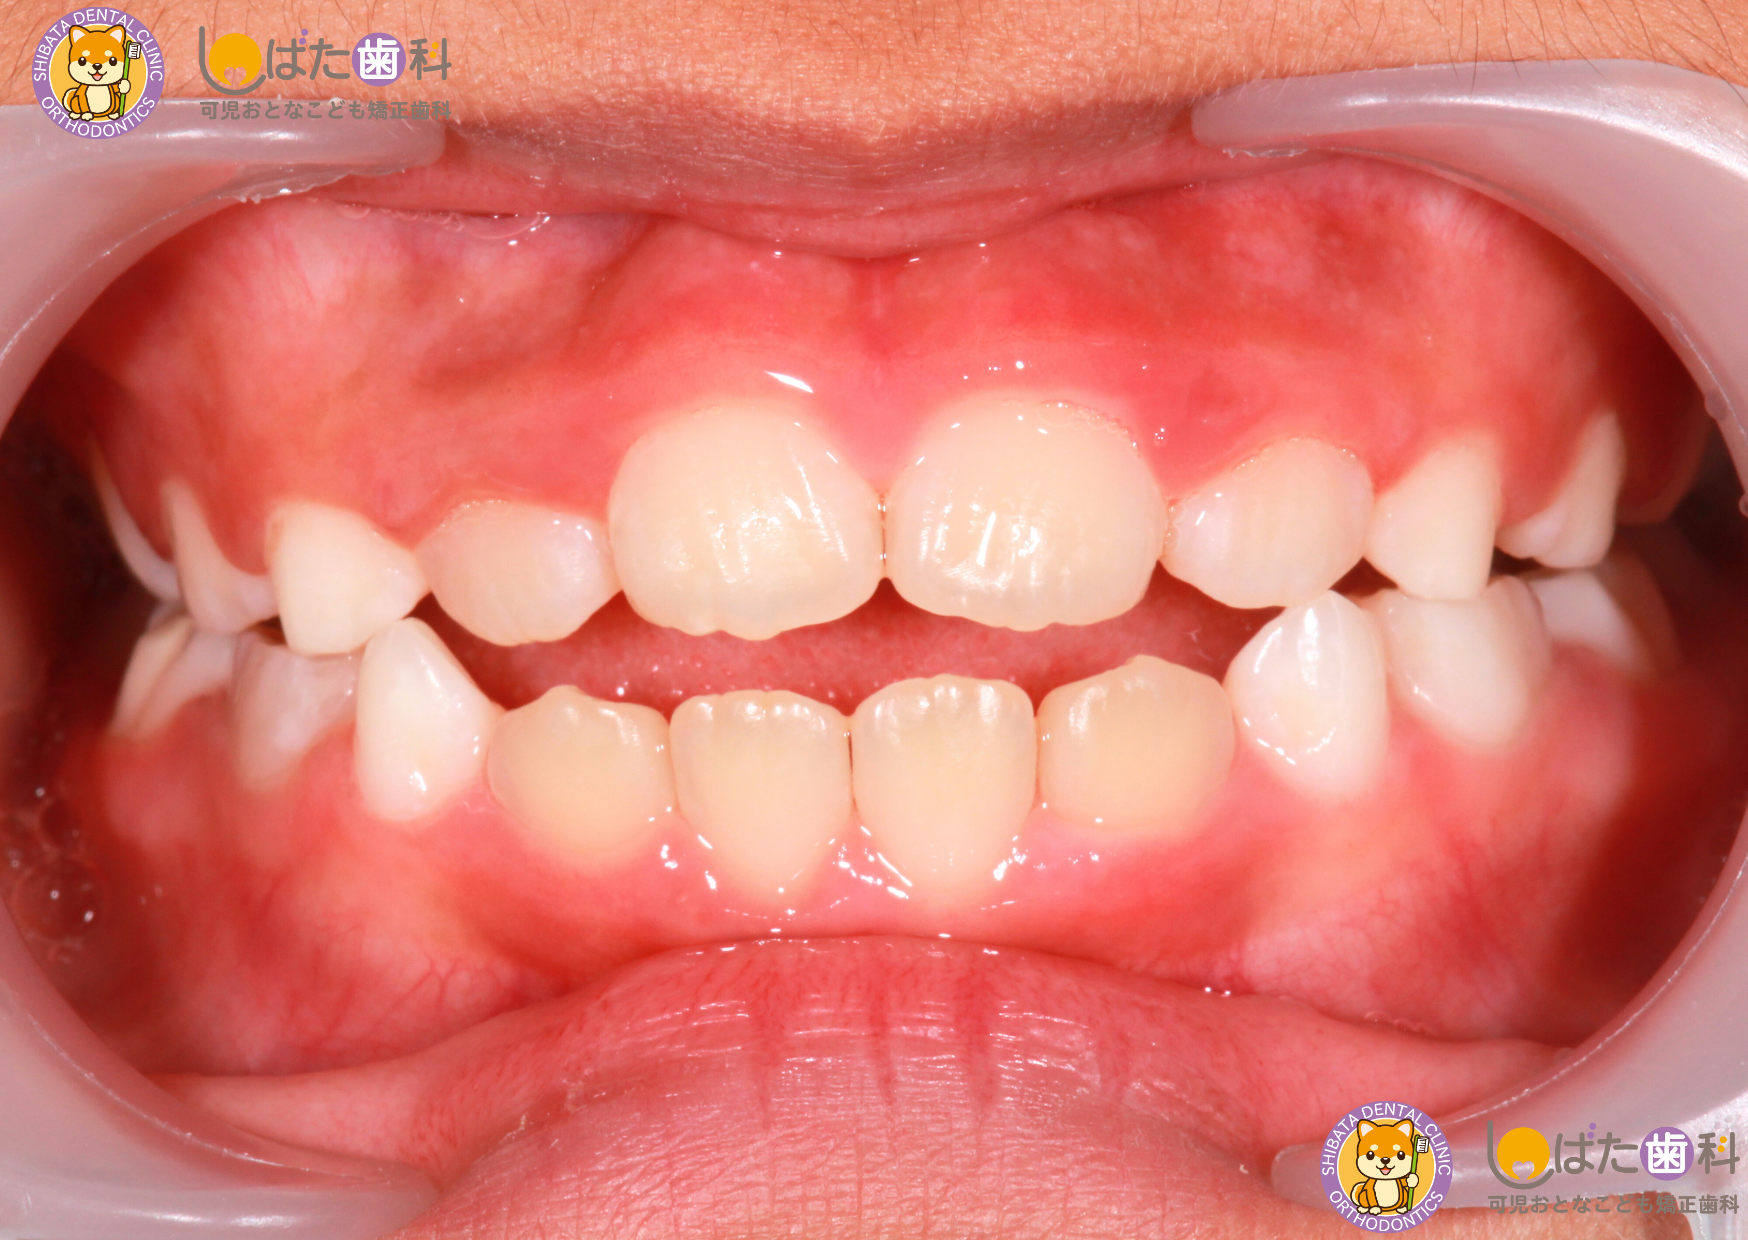

・叢生(歯列の凹凸)

歯の大きさと顎の大きさのバランスがとれておらず、歯が部分的に重なっている状態を「叢生」といいます。八重歯なども叢生の一種です。